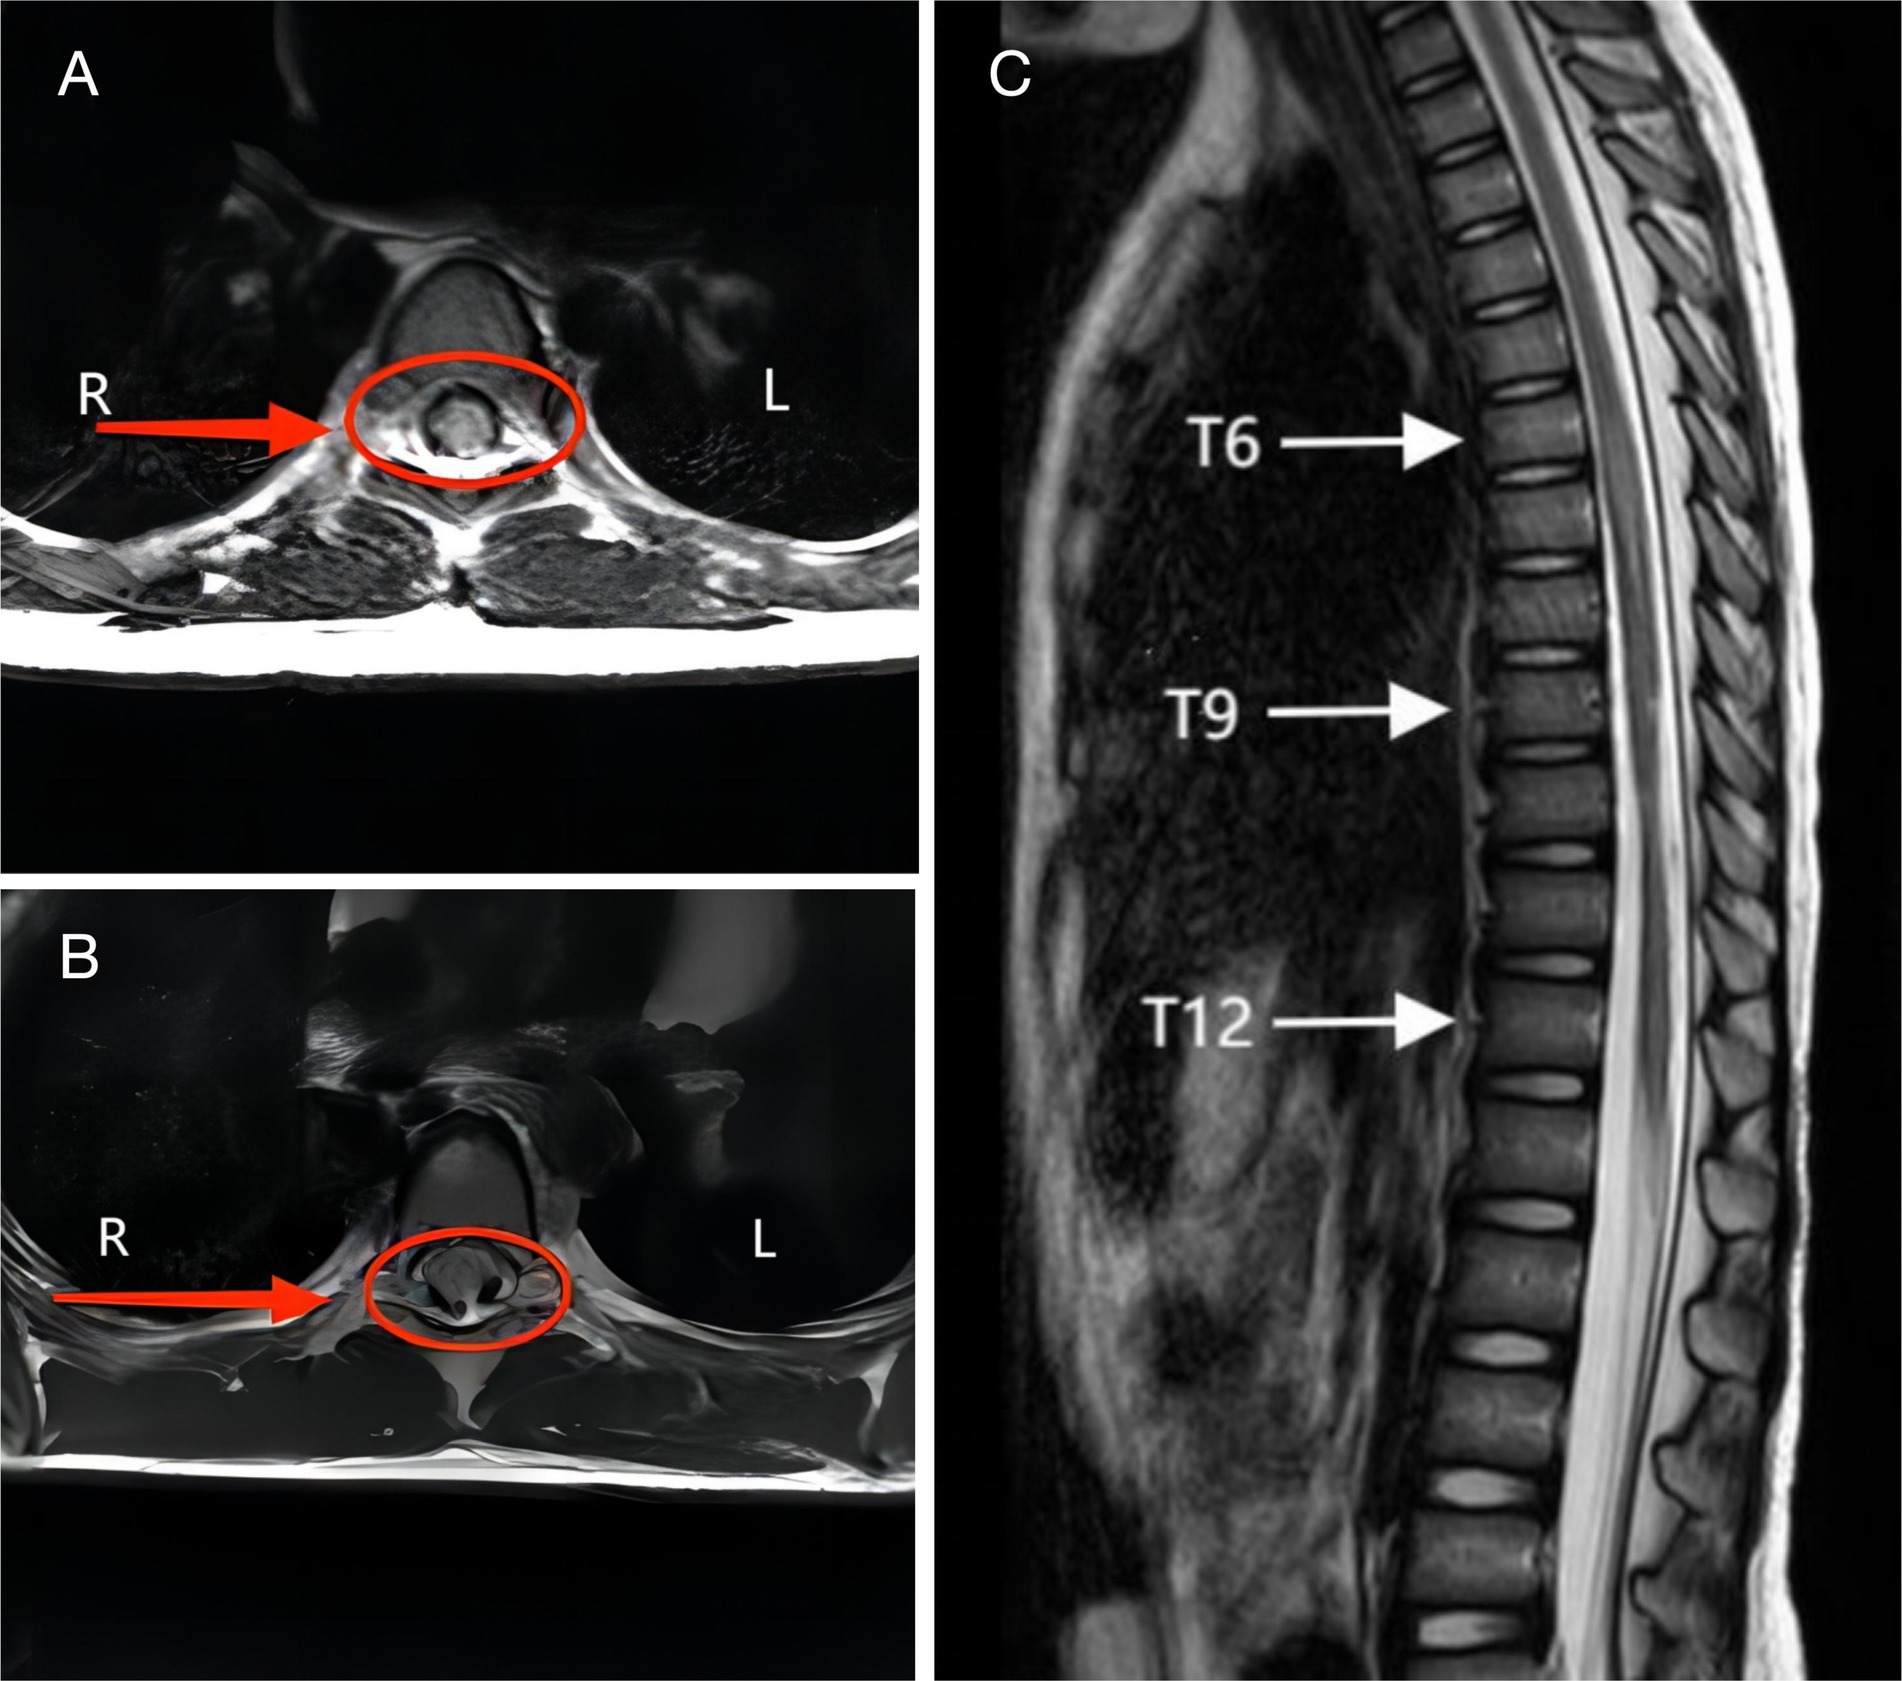

All patients underwent whole spine radiography, CT and MRI imaging. No vertebral fracture or subluxation was found on X-ray film or CT. MRI examination did not show any abnormalities in the morphology and signal of the vertebral body and intervertebral discs. In this study, the characteristics of spinal venous hypertension could be seen on some T2-weighted imaging images, intramedullary high-intensity signal and flow voids resembling dots or coils around cord (Figures 2A,B). In some cases, long T2 signals were seen in the spinal cord in sagittal sequences, suggesting spinal edema (Figure 2C). In addition, in some of the children, the spinal cord morphology was reduced in the sagittal sequence, suggesting spinal atrophy (Figure 2C).

Figure 2

(A) A 5-year-old female developed lower limb pain and numbness 30 min after performing a backbending exercise, diagnosed with complete spinal cord injury. MRI T2WI of the T7 spinal cord showed the presence of the flow void with a coil sign around cord. (B) A 6-year-old female experienced immediate inability to move both lower limbs after a backbending exercise, diagnosed with incomplete spinal cord injury. MRI T2WI of the T10 spinal cord showed the presence of the flow void with a dot sign around cord. (C) A 5-year-old female showed immediate loss of movement in both lower limbs after a backbending exercise, diagnosed with complete spinal cord injury. MRI T2WI shows spinal cord edema in T6-12 and spinal cord atrophy in T9-12.